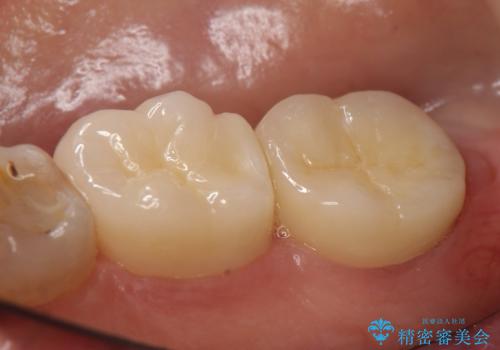

右下6、7の古い詰め物および虫歯を除去後、オールセラミッククラウンによる補綴を行いました。

今回用いたオールセラミッククラウンはジルコニアフレームという白い素材の上にセラミックを盛っているため、審美性が非常に高いのが特徴です。

また、ジルコニアは人工ダイヤモンドの材料にも使われているほど高い強度を持っており、そのためオールセラミッククラウンは審美性だけでなく、奥歯やブリッジの補綴も可能とするクラウンです。